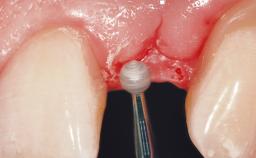

Early Placement of an Implant in a Maxillary Right Central Incisor Site

This 41-year-old female patient was referred to the clinic for the replacement of the right central incisor, since the tooth had developed a root fracture in the long axis that made extraction necessary. The healthy, non-smoking patient was first seen with the tooth still in place. A detailed Esthetic Risk Assessment was performed.The patient was worried about her dental esthetics and had high expectations for a successful treatment outcome from an esthetic point of view. The patient had a medium lip line that displayed parts of the gingiva in the anterior maxilla upon smile.

Soft Tissue Contour and Volume Slightly compromised